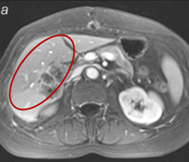

Resonancia magnética antes del tratamiento